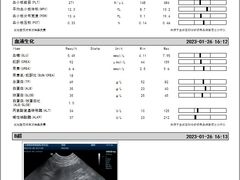

• -爱侣宠医·鹦鹉专科·小型哺乳类·异宠专科(灵石路店)

康斯旦丁 | 23-02-07

报错